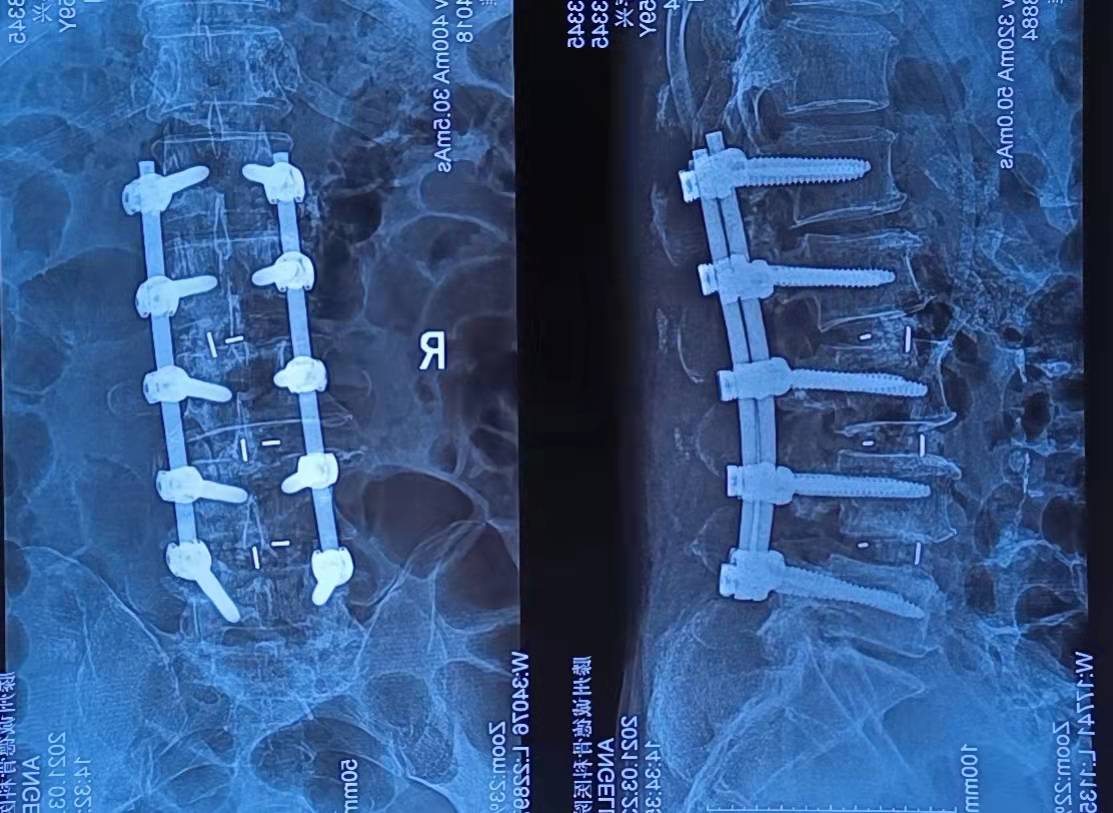

患者秦存興,男,59歲,腰痛多年勞累后加重,近一年來感腰痛伴雙側(cè)臀部、左大腿外側(cè)、小腿外側(cè)及右足麻木,行走50米后即感雙下肢疼痛劇烈,病痛的折磨給患者的生活帶來了很大的痛苦,讓他對(duì)未來失去了信心。來到誠(chéng)德骨科醫(yī)院

經(jīng)查體、X片、CT及核磁共振檢查后確診為腰椎管狹窄癥,腰椎退變性滑脫,與患者充分溝通后決定行腰1-腰5減壓植骨內(nèi)固定術(shù)

術(shù)后患者癥狀立刻減輕,術(shù)后第三天下地行走,一月后復(fù)查患者步態(tài)如常,對(duì)治療結(jié)果非常滿意